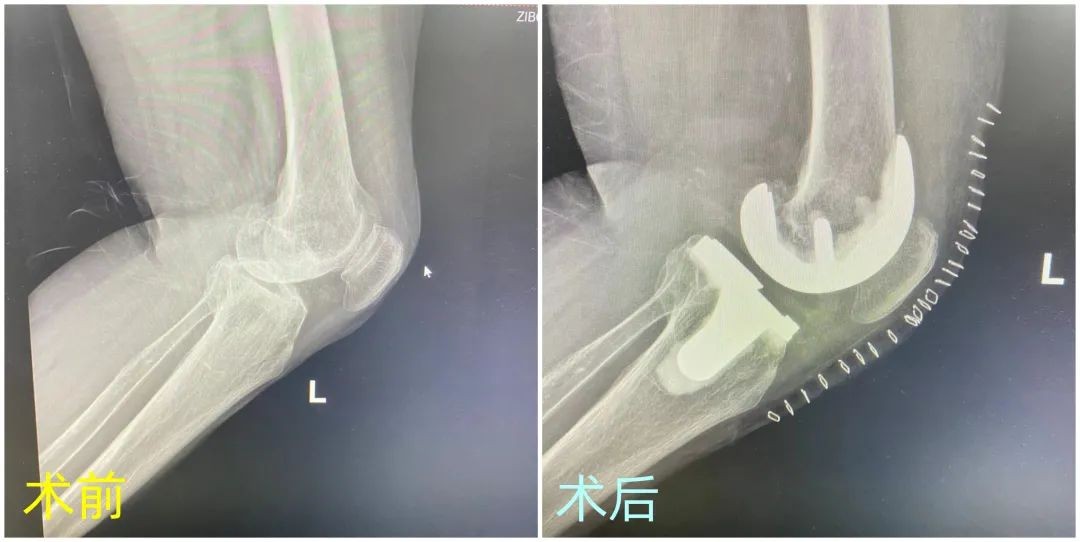

早下地、早活动已经内化到骨三科每一项治疗措施中。在整个治疗过程当中,通过医生的合理“排兵布阵”,精准把握好疾病的特征、掌握疾病发展脉络,再施以多学科的精准治疗,展现了医者对精准诊疗的追求。“医生反复告诉我在这儿做手术不疼,我开始半信半疑,哪有手术不疼的,现在做完没想到真的不疼,医生没有骗我啊!”接受膝关节置换治疗后的孙女士笑呵呵的说道。据悉,孙女士今年73岁,左膝关节疼痛多年,曾经宁愿忍受长期疼痛也不愿做手术。

骨三科主任吕文涛解释,“所谓‘无痛’即通过完善的疼痛评估、及时的镇痛干预,帮助患者能够享受‘无痛治疗’;通过术前、术中、术后加大抗凝实现少出血,这就是‘无血’的内涵。”